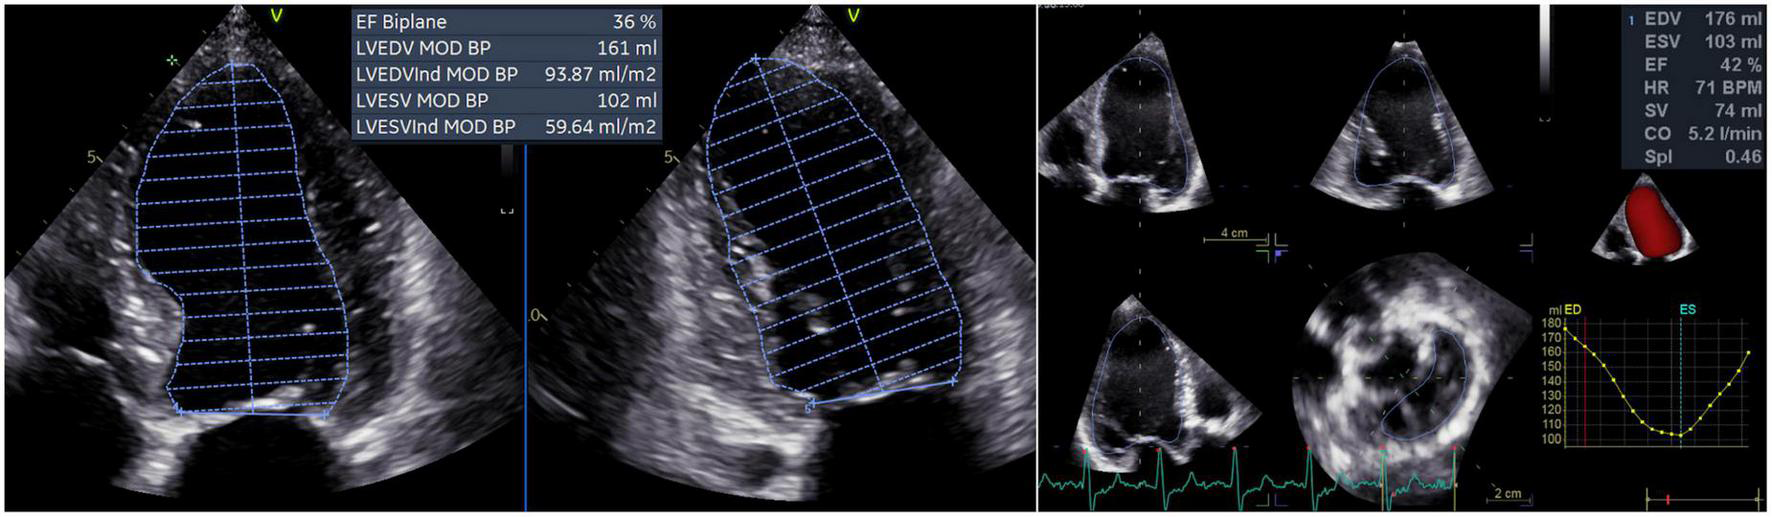

From the apical four- and two-chamber views, the 2D LV volumes and EF were measured offline by a single experienced operator using the biplane method of disks’ summation (modified Simpson’s rule, Figure 1) (17). 3DE datasets of the LV were obtained from the apical approach using multi-beat full-volume acquisition during breath-holding and taking care to encompass the entire LV cavity in the dataset (16, 21). 3D LV volumes and EF (Figure 1) were measured offline by a single experienced operator using a dedicated software package for the LV analysis (4D AutoLVQ, GE Healthcare, Horten, NO). Measurement workflow started with the semi-automated detection of the LV endocardial borders. When needed, manual editing was used to optimize the endocardial contour identification (22). To trace the endocardial borders of both the 2DE and 3DE datasets, the end-diastolic frame was selected as the frame before the mitral valve closure, whereas the end-systolic frame was identified as the frame before mitral valve opening.

FIGURE 1

Left ventricular volumes and ejection fraction calculated by two-dimensional echocardiography (left panel) and measured by three-dimensional echocardiography (right panel). CO, cardiac output; EDV, left ventricular end-diastolic volume; ESV, left ventricular end-systolic volume; EF, ejection fraction; HR, heart rate; LV, left ventricular; MOD BP, biplane mode; SV, stroke volume; SpI, sphericity index.